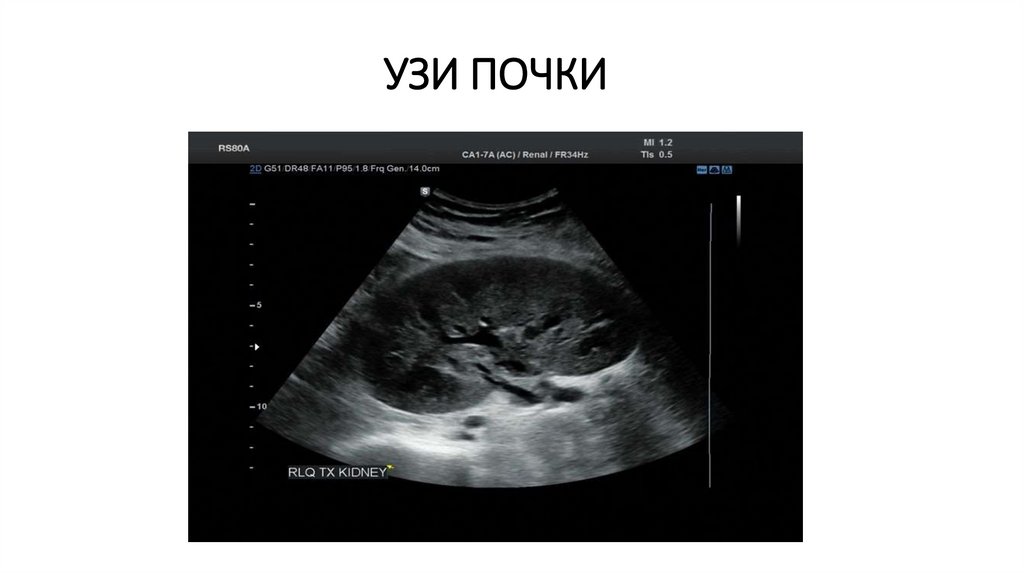

УЗИ ПОЧКИ

Органы забрюшинного пространства: почки и мочеточники, надпочечники, лимфатические узлы